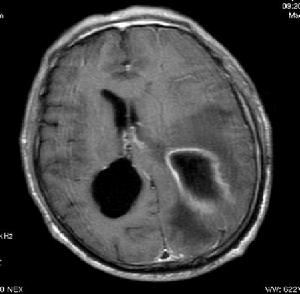

小腦腦膿腫MRI顯示1、頭顱X線平片 可發現乳突、副鼻竇和顳骨岩部炎性病變、金屬異物、外傷性氣顱、顱內壓增高和鈣化松果腺側移等。

小腦腦膿腫MRI顯示1、化膿性腦膜炎:有高熱、脈快,腦膜刺激征明顯,但無局限神經定位征,腦脊液白細胞和蛋白質增高,腦超聲檢查,腦血管造影和CT掃描均正常。